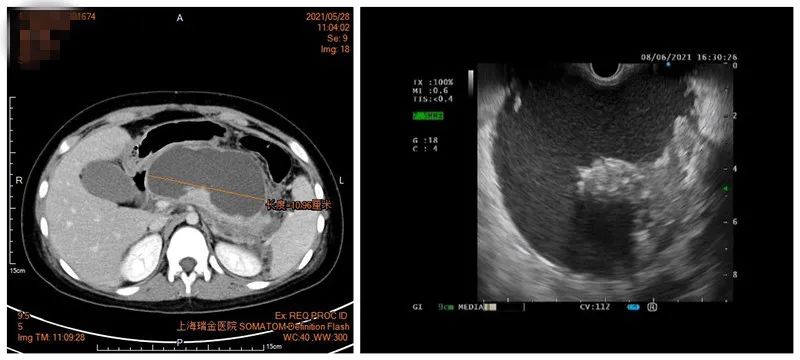

焦灼的一家人四下打听后,带着小熙直奔瑞金医院儿科,小熙的腹部超声和CT检查显示:胰腺结构失常,腹腔内胰腺的区域有大小约161×48mm的大囊肿,囊肿里面有大量坏死物,符合急性胰腺炎伴假性囊肿,儿科肖园、余熠等医生商量后,迅速联系消化科展开多学科讨论。

CT显示巨大胰腺假性囊肿,压迫胃肠道(左图)

超声胃镜显示巨大胰腺假性囊肿(右图)